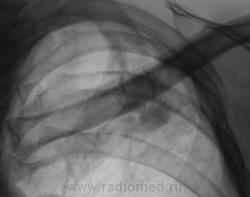

Пациент, после прохождения профилактической флюорографии "взят на контроль".  Произведено дообследование.

Я бы остановилась на множественных туберкулемах s1-2 обоих легких,Туберкулемы не однородны.за счет уплотнения,пл очаги.фиброз.

Слева туберкулома и корень подтянут Справа-очаги отсева .Динамика типичная- лечим.лечим-а туберкуломе хоть бы хны!

Туберкулёма только в С1+2 слева, как дела давно минувших дней.  Произошла реактивация туберкулёзного процесса с развитием двустороннего очагового туберкулёза. Имеется положительная динамика в виду некоторого уплотнения очагов. Таково мое мнение.